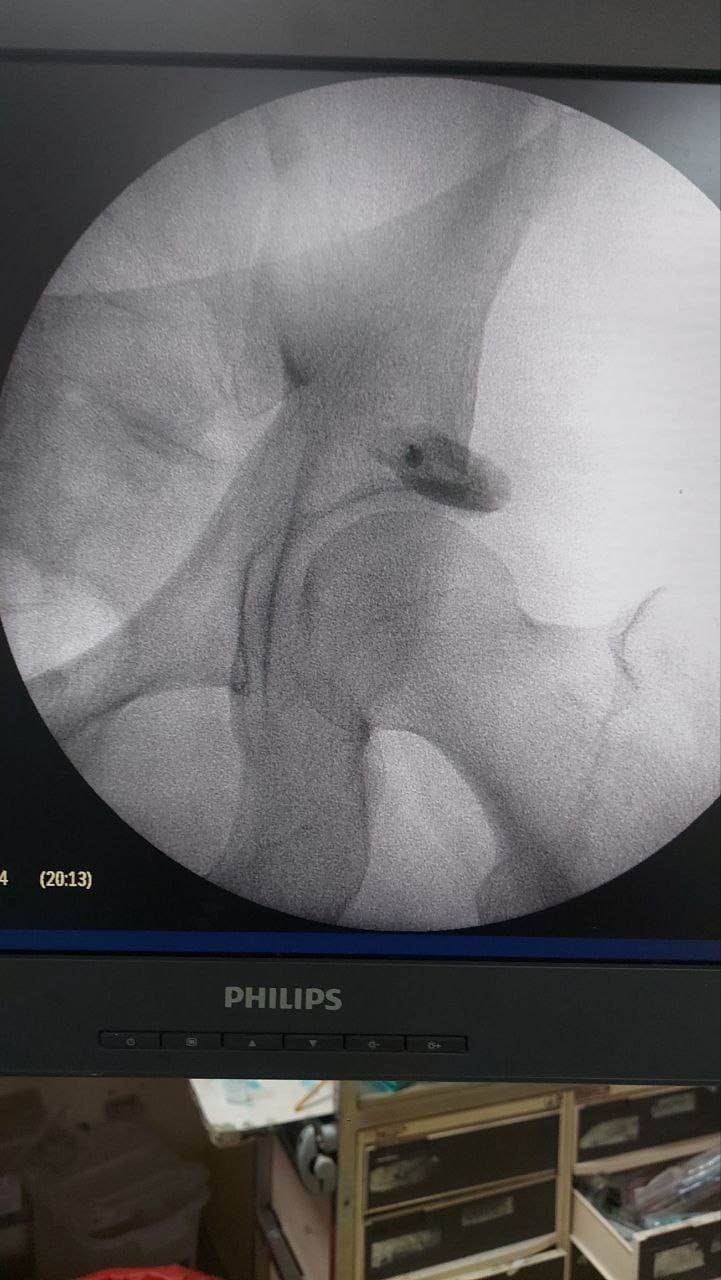

Procedures